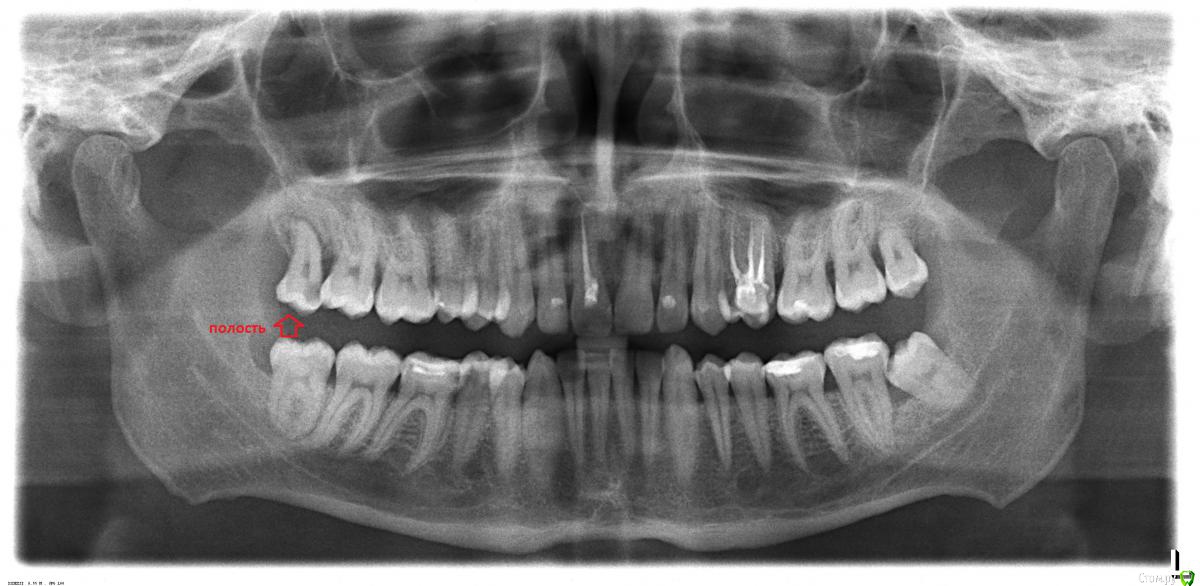

x11d15 Опубликовано 11 августа, 2016 Поделиться Опубликовано 11 августа, 2016 (изменено) Здравствуйте уважаемые врачи! Внутри полость, зуб иногда слегка побаливает при сильном накусывании боль короткая и быстро проходит, бывает очень редко. Можно или его вылечить и нужно ли депульпирование? Рот открывается довольно широко. Насколько там парадантоз серьезный рядом и вообще по десне? Изменено 11 августа, 2016 пользователем x11d15 1 Ссылка на комментарий

red_butler Опубликовано 12 августа, 2016 Поделиться Опубликовано 12 августа, 2016 Зубы мудрости Ваши, расположены не правильно, в жевании в полном объеме не участвуют. В результате не возможности выполнять полноценную гигиену, в области третьих и вторых моляров, у Вас кариес и серьезные проблемы с пародонтом. Ссылка на комментарий

x11d15 Опубликовано 12 августа, 2016 Автор Поделиться Опубликовано 12 августа, 2016 (изменено) в области третьих и вторых моляров, у Вас кариес и серьезные проблемы с пародонтом. Это уже есть или будет? Это какие по счету зубы? Мне врачи говорили еще, что центр снимка не очень информативен в силу испорченности и не очень качественен. Изменено 12 августа, 2016 пользователем x11d15 Ссылка на комментарий

red_butler Опубликовано 12 августа, 2016 Поделиться Опубликовано 12 августа, 2016 Это уже есть или будет? Это какие по счету зубы?Уже есть. Ссылка на комментарий

DmitrySH Опубликовано 13 августа, 2016 Поделиться Опубликовано 13 августа, 2016 Смотрите, у вас возникла проблема из-за невозможности адекватной гигиены между 7 и 8 зубом. Даже если сейчас все вылечить, то боли пройдут, но проблема останется. Озон, лазер и прочее тут не помогут. Выше уже все правильно сказали, спасая восьмые - угробите седьмые зубы. Ссылка на комментарий

x11d15 Опубликовано 13 августа, 2016 Автор Поделиться Опубликовано 13 августа, 2016 (изменено) Смотрите, у вас возникла проблема из-за невозможности адекватной гигиены между 7 и 8 зубом. Даже если сейчас все вылечить, то боли пройдут, но проблема останется. Озон, лазер и прочее тут не помогут. Выше уже все правильно сказали, спасая восьмые - угробите седьмые зубы. Да дело в том, что я помню что десна в том месте у меня всегда была немного вздутая еще с ранней молодости, до появления зуба мудрости, а над ней такое что то коричневое, но не кариес, а потом она просто опустилась немного, вот недавно буквально. А еще врач сказал, что там опустилась десна из за того, что кость уменьшилась чтоль или рассосалась. Там как раз в том месте, где была полость кариозная (см. выше). Изменено 13 августа, 2016 пользователем x11d15 Ссылка на комментарий